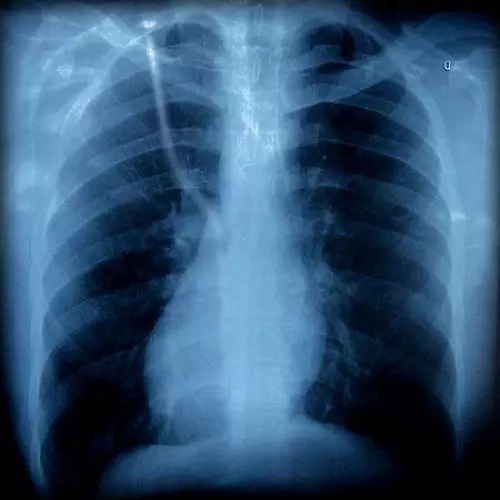

胸片有异

胸外科

咳嗽可以是由肺部肿瘤等疾病引起的,如果胸片或胸部CT上发现有可疑病变时,应该看看胸外科。一般,呼吸内科大夫也会帮忙转诊的。